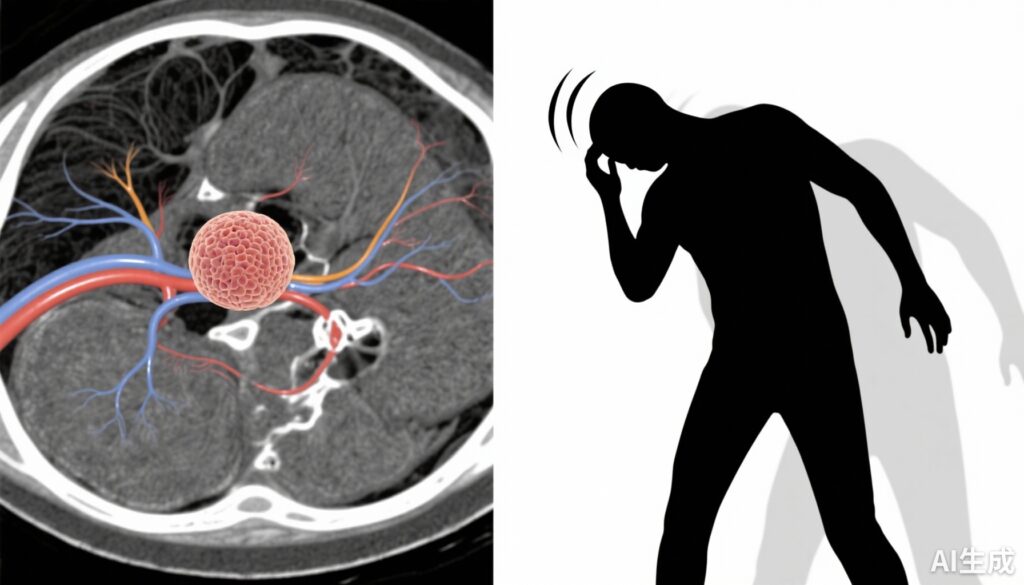

前庭神経鞘腫(VS)、または聴神経腫瘍は、前庭蝸牛神経のシュワン細胞から発生する良性で通常は成長速度の遅い腫瘍です。患者は一般的に難聴、耳鳴り、めまいなどの訴えがあり、これらの症状は生活の質に著しく影響を与えます。難聴と耳鳴りは広く研究されていますが、VSにおけるめまいの決定因子や特性はまだ十分に理解されていません。めまいは、めまい、バランスの乱れ、または主観的な不安定感を含むことができ、これらはすべて障害や転倒リスクに寄与します。不安などの心理的要因は慢性神経学的疾患で一般的であり、症状認識と重症度を調整する可能性があります。めまいに関連する要因を特定することで、より良い症状管理と個別化されたケア戦略につながる可能性があります。